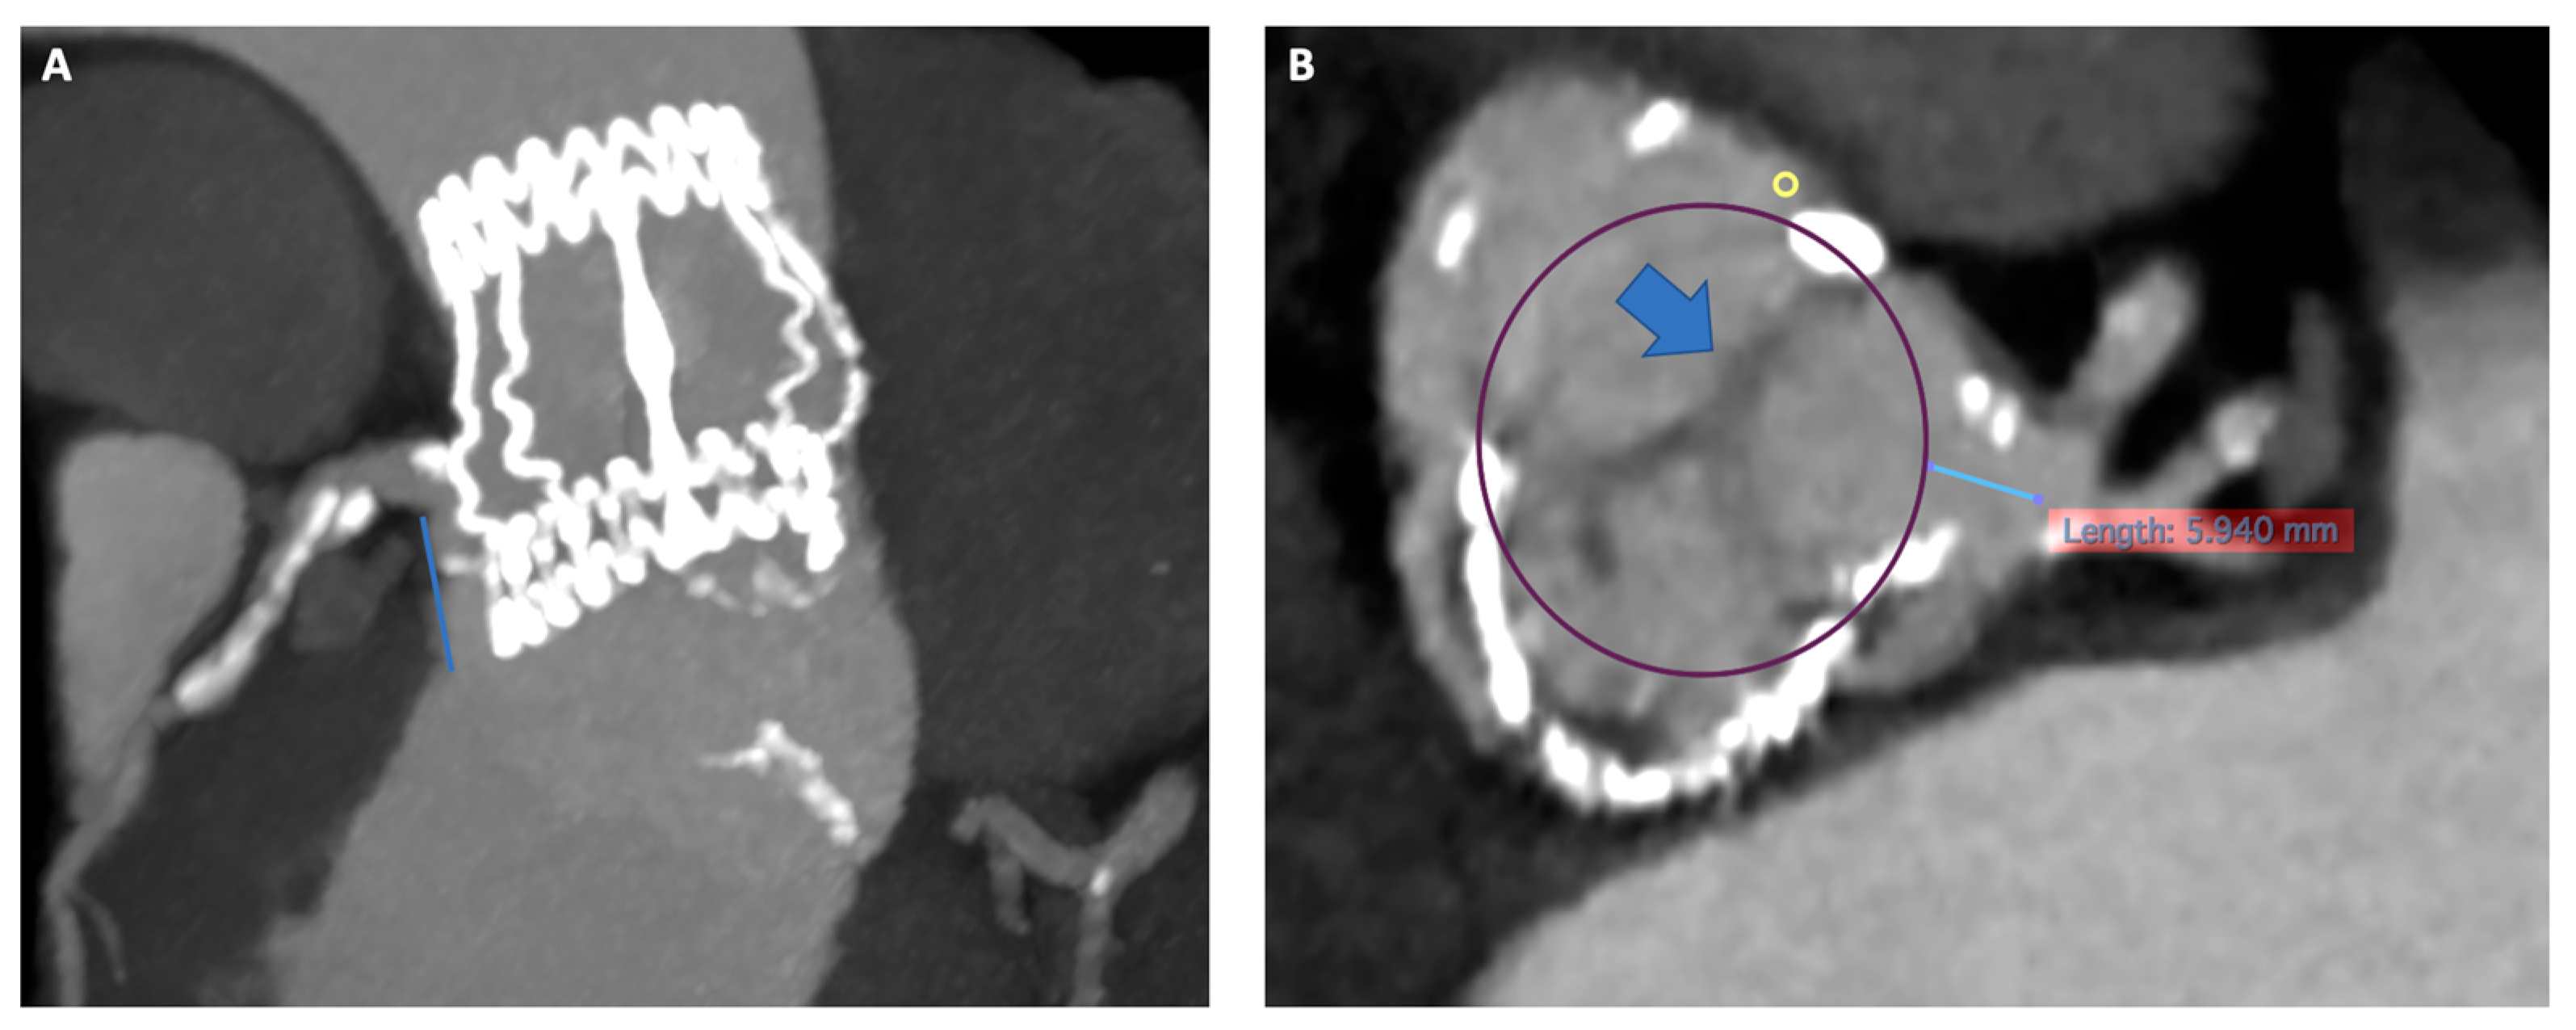

Figure 1 and Figure 2 illustrate key moments in pre-procedural planning for TAVR in SAVR. See also Supplementary Videos S1 and S2.

Figure 1.

Pre-procedural CT scan simulating a 26 Sapien 3 Ultra implantation showing good sealing of the THV prosthesis to the hinge points of the Perceval bioprosthesis at different heights (LVOT in panel (A) and SOV in panel (B)). CT: computed tomography; THV, transcatheter heart valve; LVOT, Left ventricular outflow tract; SOV, Sinus of Valsalva.

Figure 2.

Risk of coronary artery obstruction evaluation at pre-procedural CT scan. Panel (A) Permissive height of LCA (18 mm). Panel (B) VTC of 5.9 mm simulating a 26 Sapien 3 Ultra with wide Sinus of Valsalva and redundant leaflet. CT, computed tomography; LCA; left coronary artery; VTC, valve to coronary ostia.